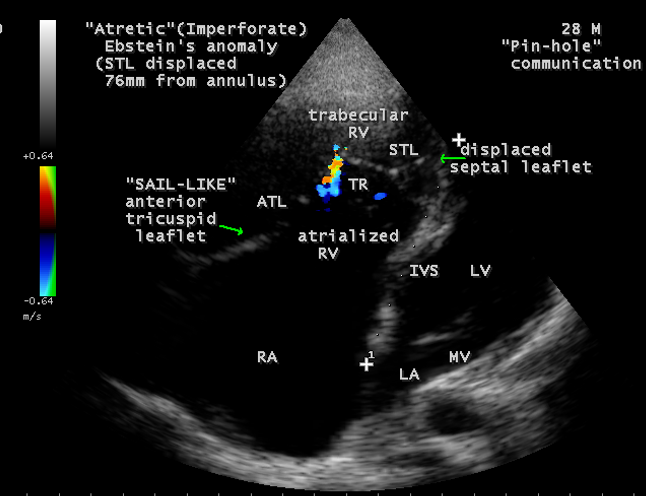

A 28-year old male presented with cyanosis and auscultation revealed a ‘sail sound’ ( loud tricuspid component of first heart sound due to increased tension developed by the large anterior leaflet as it reaches the limits of its systolic excursion- an important sign of anterior leaflet mobility), a ‘cadence’ quality of quadruple rhythm due to wide splitting of first and second sounds ( due to complete right bundle branch block), atrial and ventricular filling sounds (summation of these sounds due to prolonged PR interval). ECG revealed the features of Ebstein’s anomaly as shown in Figures 11 and 12. X-ray chest revealed the Ebstein’s configuration as shown in Figure 13. 2D echocardiography revealed a ‘sail-like’anterior tricuspid leaflet forming a ‘muscular curtain’ in between the inflow and trabecular parts of the right ventricle as an ‘imperforate membrane’ with a ‘pinhole’communication, associated with a muscular VSD (ventricular septal defect) in the proximal, atrialized compartment of right ventricle suggesting an ‘atretic” (‘imperforate’) Ebstein’s anomaly as shown in Figures 14 to 27.

Echocardiographic features Echocardiography is the diagnostic test of choice for Ebstein’s anomaly and the first echocardiographic diagnosis was reported by Lundstrom in 1969. The first diagnostic criteria for Ebstein’s anomaly using a multi-crystal two-dimensional system was defined by Hagan in 1974 [33] and they were able to recognize the apical displacement of the septal tricuspid leaflet and an elongated anterior tricuspid leaflet with increased excursion. The septal leaflet of the tricuspid valve attaches chiefly to the ventricular septum , but part of its basal attachment is to the posterior wall of the right ventricle [34] and it normally exhibits a slight but distinct apical displacement of its basal attachment to the central fibrous body compared to the mitral valve. The distal displacement of septal origin of tricuspid valve seems to be the best echocardiographic criterion as the characteristic sign for Ebstein’s anomaly and the degree of maximal displacement in normal hearts varies considerably with a mean difference of approximately 6 mm with mitral valve. To define the anatomic severity of Ebstein’s anomaly, four-chamber view is the best to demonstrate the apical displacement of septal tricuspid leaflet [35]. The ratio between the mitral-to-apex distance and the tricuspid-to-apex distance varies from 1 to 1.2 in normal subjects and 1.8 to 3.2 in patients and it is 3.6 as in Figure 18 with Ebstein’s anomaly. The true distance in the level of insertion of atrioventricular valves is obtained by substracting the tricuspid-to-apex distance from the mitral-to-apex distance with a mean value of 27.25 ± 12 mm in patients with proven Ebstein’s anomaly and it is 60 mm as shown in Figure 18 compared to reference group (5.7 ± 2 mm). Kambe and coworkers calculated the distance between both atrioventricular valves directly as a mean value of 21 mm with a range of 14 to 32 mm [36]. A maximum difference in the level of valve insertion of >15 mm in children and >20 mm in adults is discriminated between normal and Ebstein’s anomaly [37],[38]. Despite this fact, a patient with an ‘unequivocal’ Ebstein’s malformation can be encountered in whom the diagnosis cannot be made with certainity solely on the basis of apical displacement of the septal tricuspid valve leaflet. Occasionally, the leaflet attaches to the trabecular part rather than the inlet part of the septum, the conventional four-chamber view will not reveal any septal insertion as shown in Figures 28 and 29.

The anterior tricuspid leaflet is not involved in the process of downward displacement, it may be abnormally inserted occasionally and Shiina, et al documented the apical displacement of anterior tricuspid leaflet in 14% of cases echocardiographically [39]. The anterior leaflet forms a large, sail-like intracavitary curtain as in Figures 14, 25 and contains muscular strands instead of consisting entirely of a fibrous membrane as in the normal tricuspid valve [40]. It is potentially mobile with a brisk sail-like movement as shown in Figure 21 to 24 [41], free bloating with a ‘whipping motion’ across the right ventricular outflow tract (RVOT) as shown in Figure 26 and in some cases, the movement is restricted due to its adherence to the ventricular wall as in Figure 1 and 2, 4 and 9. It is often fenestrated, may in part be musculaized , inserting into the trabeculations of the right ventricle (RV) as in Figure 28 and rarely, the anterior leaflet forms an ‘atretic’ membrane that spans the midportion of the right ventricular cavity as in Figure 16.

The tricuspid orifice is typically incompetent as in Figures 3, 5 and 10, occasionally stenotic, and rarely imperforate as in Figure 16 [44],[45]. The true anatomic tricuspid annulus occupies its normal position at the right atrioventricular junction and it is less well defined than in a normal heart. The annulus tends to be appreciably dilated and contribute to the development of valvular incompetence. In extreme downward displacement of posterior and septal leaflets, the closure of the tricuspid annulus depends on the size and potential excursion of anterior leaflet. When the chordal attachments are short and the leaflets contain multiple or large fenestrations, adequate valve closure is impossible to achieve and varying degrees of regurgitation results. Color flow imaging and Doppler interrogation can establish the relatively low velocity regurgitant flow as in Figure 6, which begins at the level of the displaced septal and posterior leaflets as in Figures 5 and 10 and courses through the atrialized right ventricle into the right atrium proper as shown in Figure 5. Tricuspid regurgitation increases by annular dilatation [46]. During contraction of the atrium, the atrialized portion of the right ventricle balloons out and acts as a passive reservoir. Functional improvement of right ventricle depends on the severity of tricuspid regurgitation and on the ratio of the combined areas of right atrium and atrialized right ventricle relative to the areas of functional right ventricle and left ventricle [47]. Celermajer, et al described an echocardiographic grading score for neonates with Ebstein’s anomaly as shown in the Table 5 [48].

Ebstein’s original case was an example of obstruction at the tricuspid orifice by a membrane dividing the right ventricle into two halves as shown in Figure 16 of a 28-year old cyanotic male with ECG and X-ray characteristics as in Figure 11 to 13. suggesting an advanced spectrum of Ebstein’s malformation , necessitating RV exclusion techniques such as Starnes’ procedure. The florid case of Ebstein’s anomaly with the insertion of leaflet tissue along with ventricular walls as a ‘blanket’ as in Figures 28 and 29 in a 30-year old cyanotic male may go for an initial palliation with bidirectional Glenn shunt (cavopulmonary anastomosis). The other variants of moderate degree of leaflet tethering with varying degrees of regurgitation, but an intact basal leaflet attachments with atrioventricular junction as in Cases 1 and 2 may need a definite repair. In Ebstein’s mitral valve as in Figure 32 in a 10-year old boy, the downward displacement of functional annulus > 0.8 cm/m2 is not particularly striking and tends to affect the septal leaflet (anterior mitral leaflet) alone. The valve is thickened and mildly regurgitant due to rheumatic involvement rather than an anatomic cause.